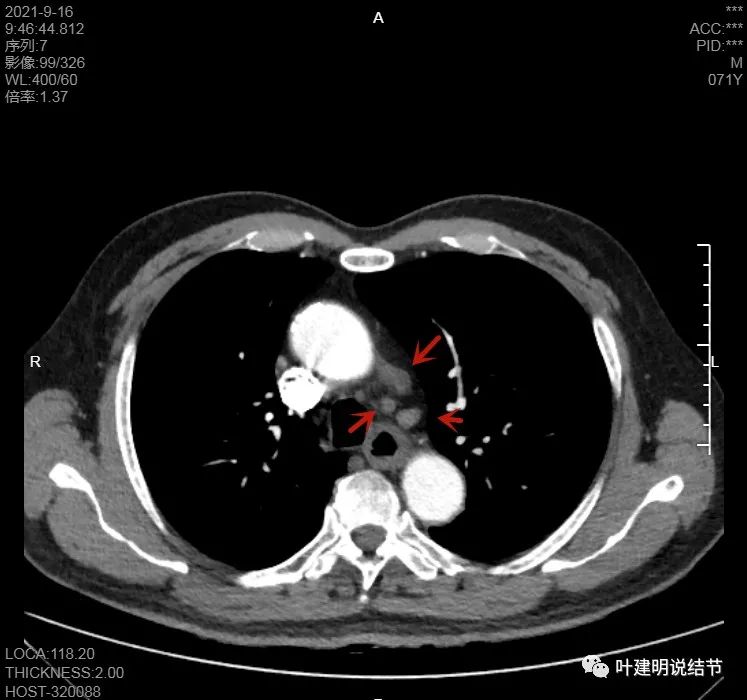

上图示病灶在左下叶,红色所指的与绿色箭头所指的是两个病灶,不相连的,实性结节

左下病灶在增强CT中强化不明显,但有肺门区肿大淋巴结,而且近3厘米大。同事叫我看片子的时候,本来只先看左下病灶处,以为是良性结节。但翻到肺门区,发现有如此大的肿大淋巴结,那这个原发灶则肯定是恶性的了!我们先来看纵隔窗的淋巴结情况:

主动脉弓下有淋巴结,但不大

左肺门区淋巴结肿大